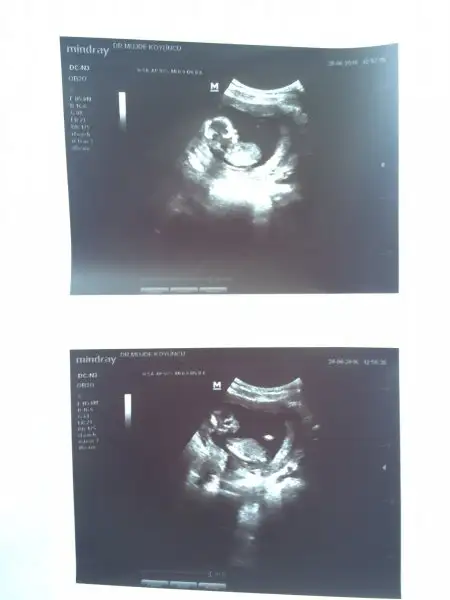

Kız benceMerhaba ocak anneleri ; Allahım hepimize sağlıklı sıhhatli evlatlarımızı kucağımıza almayı nasip etsin inşallah bu da benim miniciğim Şu an sadece bu fotolar var yanımda Cinsiyet tahmini bende alabilirmiyim?

Merhaba canlar anca yaziyorum bebişimiz çook iyi çok şükür ikili taramayı kaçırdık malesef geç kaldık. artık 19. hafta ayrıntılıyı bekleyeceğiz ama doktorum herşeyi çok güzel görünüyor dedi ense kalınlığı olması gerektiği gibi için rahat olsun dedi. veee evet söylüyorum kız geliyoor13+3 üz bu arada cordeliac S sevyeter C candy1907